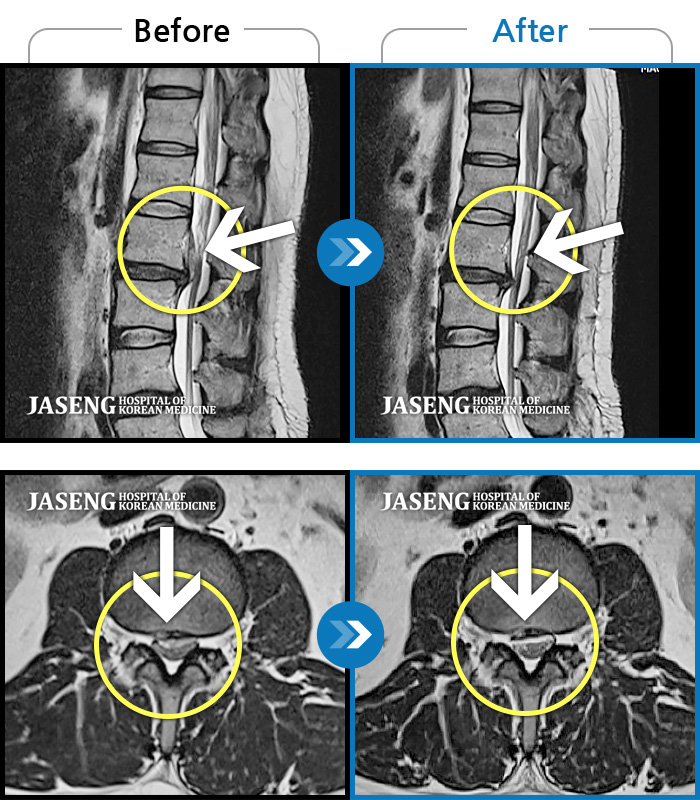

Before

After

허리통증이 심해서 숙이기 어렵고 차에서 내리기 힘들었습니다.

2021.01.06 ~ 2025.03.10